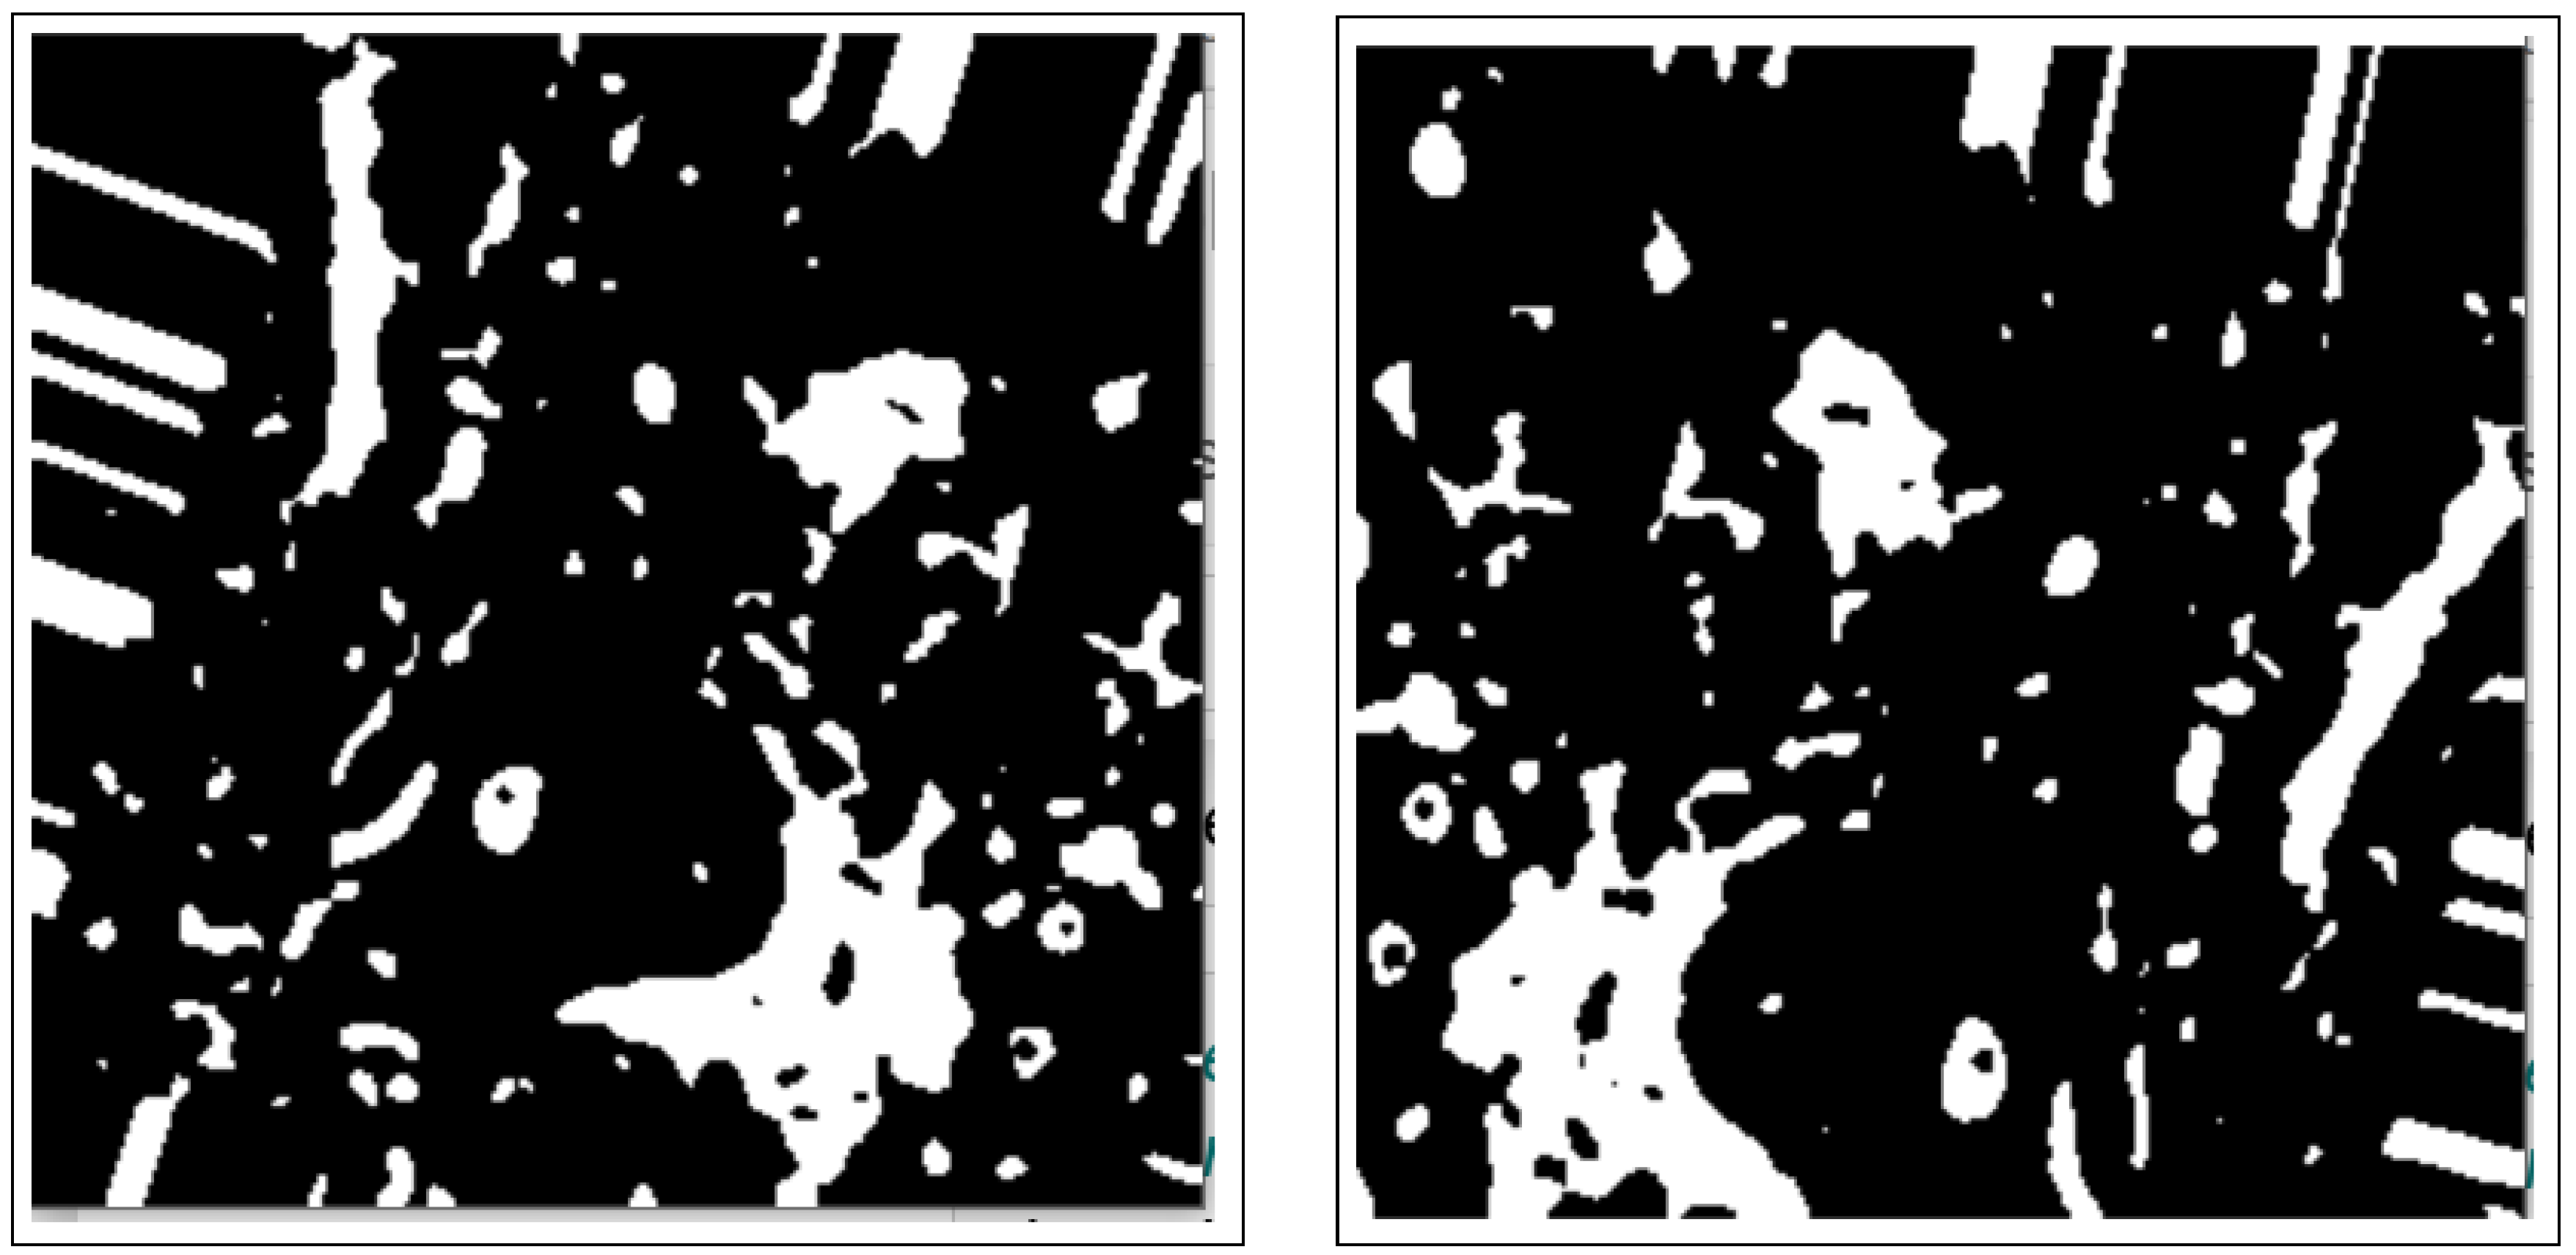

- Morphology operations enhance the image by highlighting important features. The connected components analysis method is used to group components with similar characteristics and assist in separating overlapping and non-overlapping objects.

3.2.2. Morphology Operations

3.3.1. Connected Components Analysis